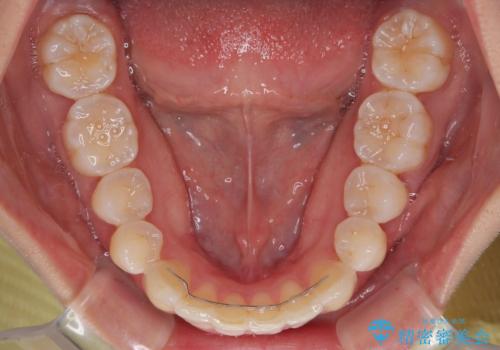

前歯のデコボコを治したい インビザライン矯正

- 上下前歯の叢生を気にして来院された患者様です。

インビザラインでの治療を希望されていて、デコボコの程度が中等度であり、安価なパッケージにて対応可能と判断されたため、インビザライン・モデレートを用いて矯正治療を行うこととしました。

インビザライン・モデレートは、製作できるアライナーの枚数に制限があるため、移動可能な量に限りがあるものの、インビザライン・ライトよりも枚数が多いため、幅広い症例に対応可能です。